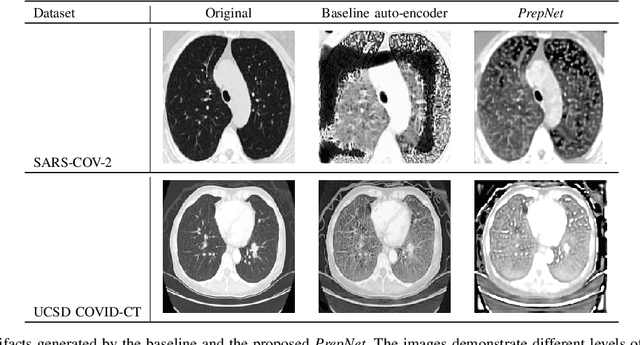

Abstract:With the spread of COVID-19 over the world, the need arose for fast and precise automatic triage mechanisms to decelerate the spread of the disease by reducing human efforts e.g. for image-based diagnosis. Although the literature has shown promising efforts in this direction, reported results do not consider the variability of CT scans acquired under varying circumstances, thus rendering resulting models unfit for use on data acquired using e.g. different scanner technologies. While COVID-19 diagnosis can now be done efficiently using PCR tests, this use case exemplifies the need for a methodology to overcome data variability issues in order to make medical image analysis models more widely applicable. In this paper, we explicitly address the variability issue using the example of COVID-19 diagnosis and propose a novel generative approach that aims at erasing the differences induced by e.g. the imaging technology while simultaneously introducing minimal changes to the CT scans through leveraging the idea of deep auto-encoders. The proposed prepossessing architecture (PrepNet) (i) is jointly trained on multiple CT scan datasets and (ii) is capable of extracting improved discriminative features for improved diagnosis. Experimental results on three public datasets (SARS-COVID-2, UCSD COVID-CT, MosMed) show that our model improves cross-dataset generalization by up to $11.84$ percentage points despite a minor drop in within dataset performance.